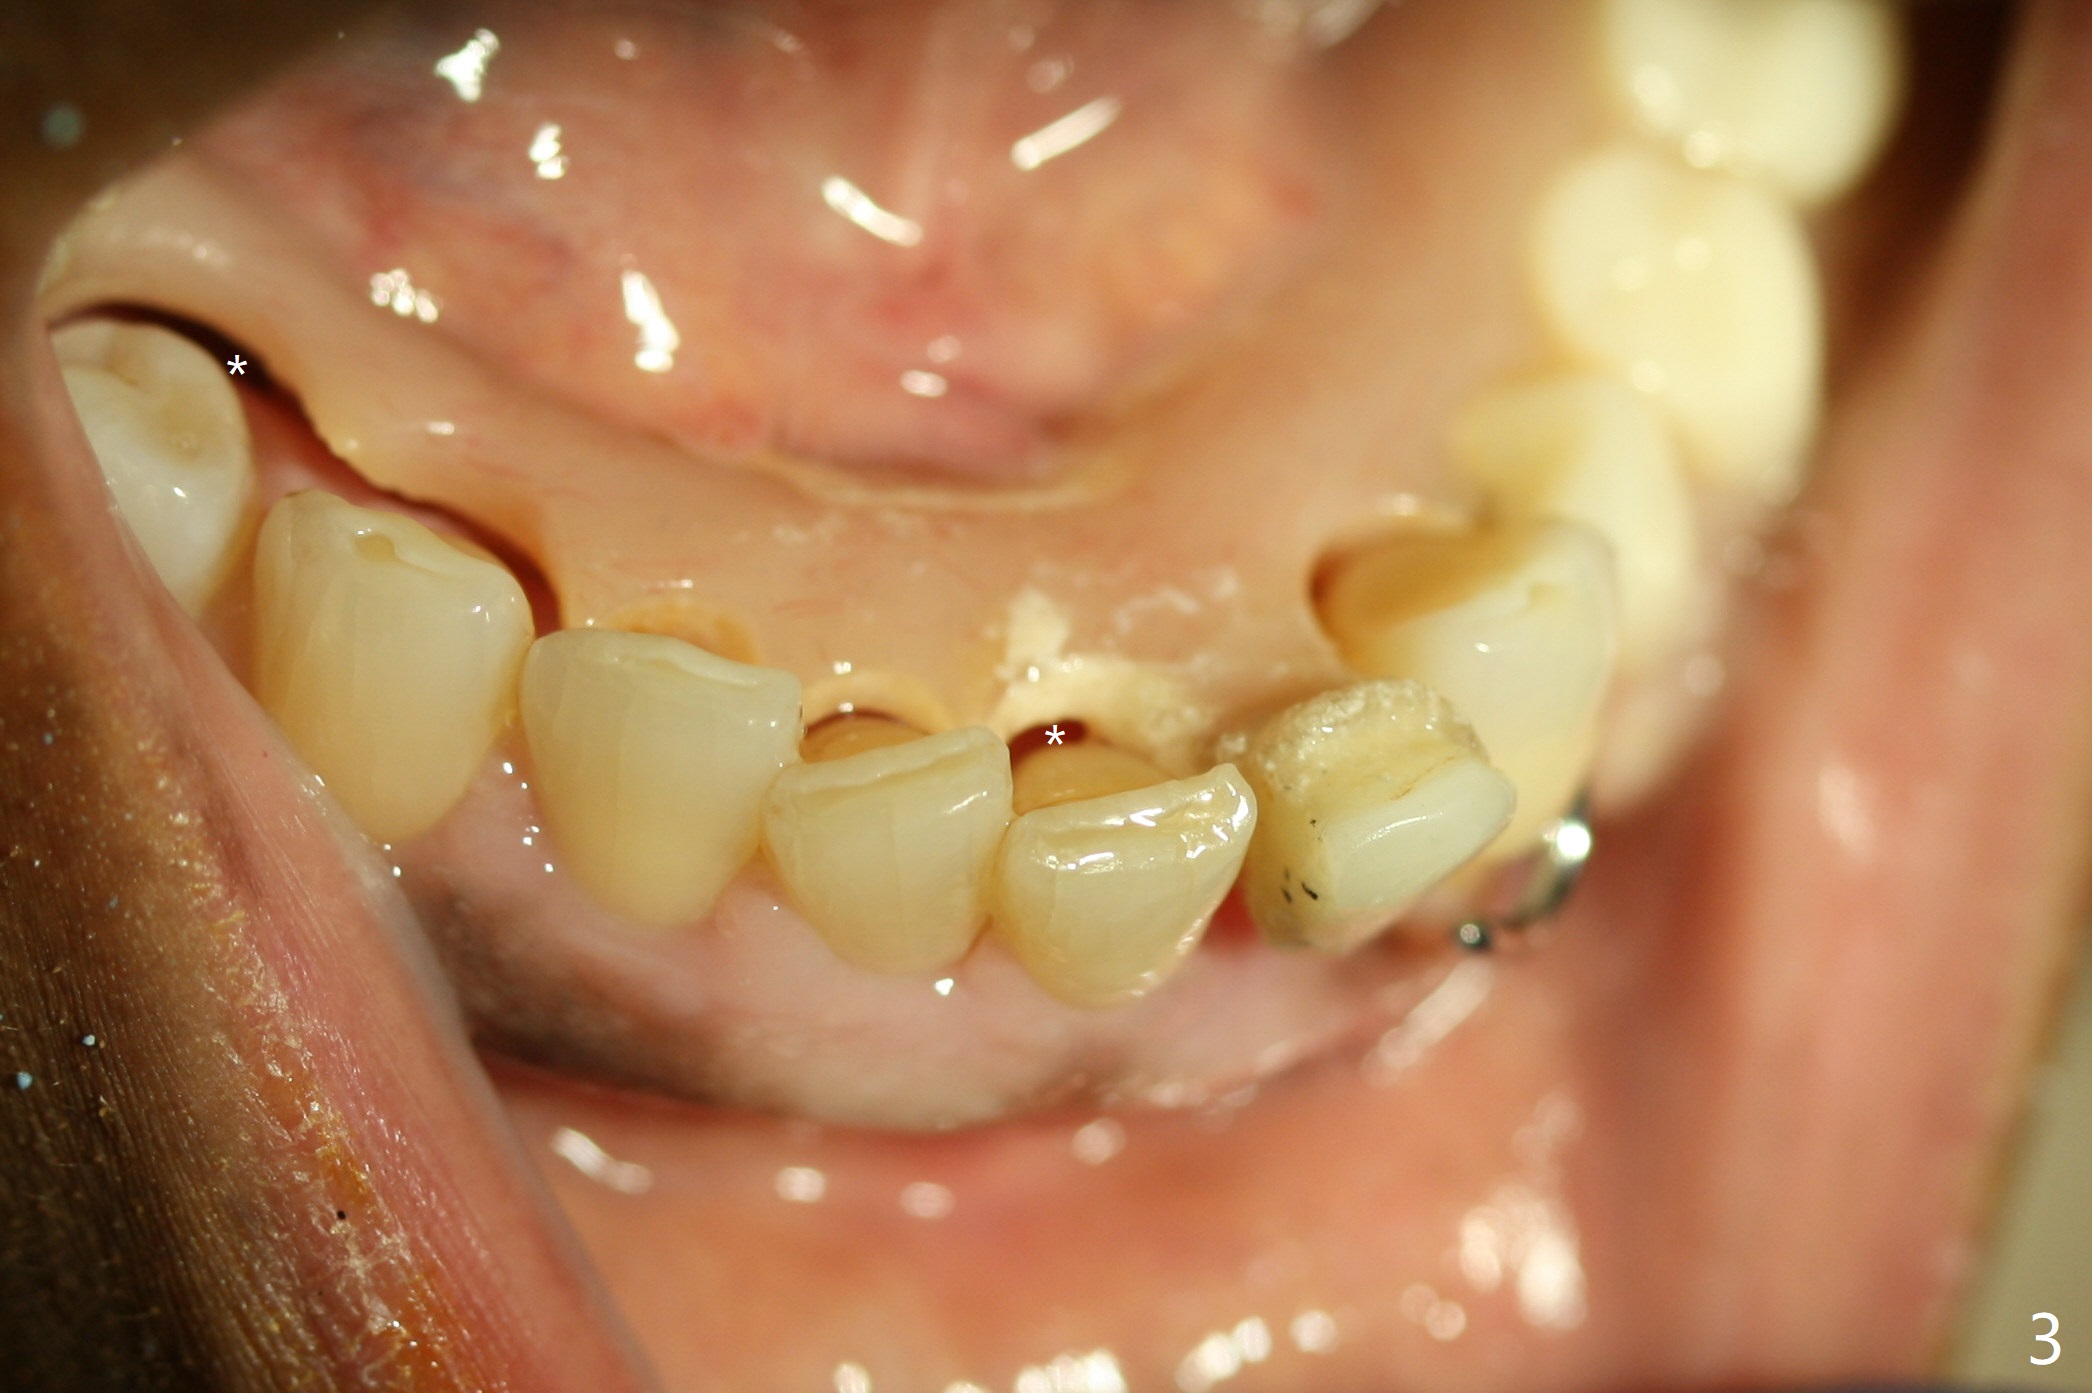

The inflammation around the tooth #22 (Fig.1 *) and mobility may be related to trauma from the only clasp of the lower flipper (Fig.2). The latter is loose with space underneath (>) and laterally (Fig.3 *). The distobuccal plate is defective upon extraction; the osteotomy is initiated in the mesiolingual slope of the socket (Fig.4) with ~ 6 mm native bone. When a 3.8x15 mm dummy implant achieves insertion torque of 50 Ncm, the insertion is incomplete with apical space (Fig.5 *). The definitive implant (3.8x13 mm) closes the apical space and obtains insertion torque >55 Ncm; a ball abutment with 2 mm cuff seems to be short for retention (Fig.6). A 4.5x4(5) mm cemented abutment (Fig.7,8) seems appropriate for retention after soft reline of the lower flipper (Fig.9-11). The socket heals without bone graft exposure 8 days postop (Fig.12,13). To satisfy the patient's desire to have a white tooth, the buccal portion of the soft reline and the abutment is removed (Fig.14) and a crown form is added (Fig.15 *). The socket obliterates 3 months postop (Fig.16).